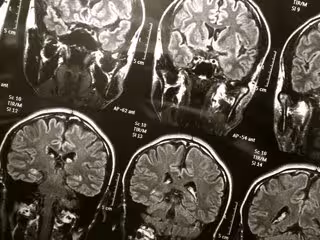

La RMN mejorada podría proporcionar información sobre el Alzheimer

FLICKR/WYINOUE - Archivo

Investigadores del Instituto Tecnológico de Massachusetts (MIT, por sus siglas en inglés), en Estados Unidos, han desarrollado una forma de mejorar dramáticamente la sensibilidad de la espectroscopia de resonancia magnética nuclear (RMN, por sus siglas en inglés), una técnica utilizada para estudiar la estructura y composición de muchos tipos de moléculas, incluidas las proteínas relacionadas con el Alzheimer y otras enfermedades.

Un área importante de interés es la proteína beta amiloide que se acumula en los cerebros de los pacientes de Alzheimer. Los científicos también planean estudiar una variedad de proteínas unidas a la membrana, como los canales iónicos y las rodopsinas, que son proteínas sensibles a la luz que se encuentran en las membranas bacterianas y en la retina humana. Debido a que la sensibilidad es tan grande, este método puede proporcionar datos útiles de un tamaño de muestra mucho más pequeño, lo que podría facilitar el estudio de proteínas que son difíciles de obtener en grandes cantidades.